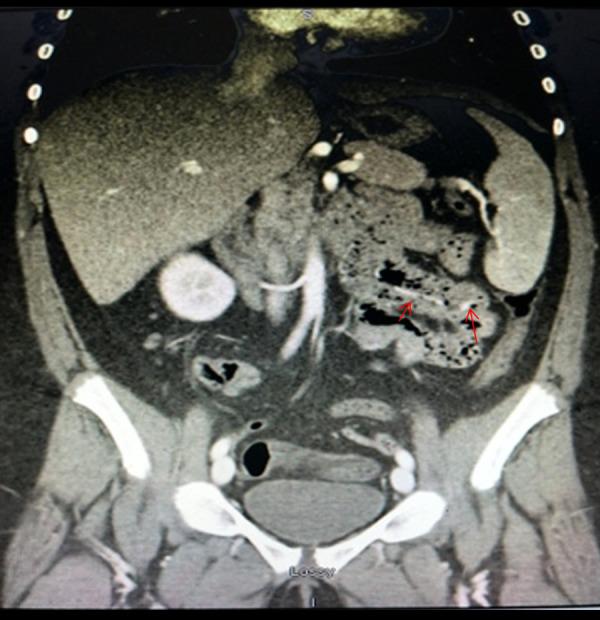

一名 14 岁的 TS 女孩因反复出现有症状的黑便就诊。最初的检查包括阴性上消化道内镜检查、阴性双内镜检查和视频胶囊内镜(VCE),VCE 显示小肠内有大量血液和小的红斑病变,但无活动性出血,梅克尔扫描阴性。CT 血管造影显示左下方肠系膜血管明显突出,单球囊内镜显示整个小肠明显的血管。在可疑出血部位放置了一个夹子。由于反复出血,患者接受了手术辅助推进式内镜检查;检查结果与弥漫性血管畸形一致。她开始使用氨甲环酸,后来转为雌激素治疗,初始表现 6 个月后无进一步的胃肠道出血、贫血或治疗相关不良反应报告。